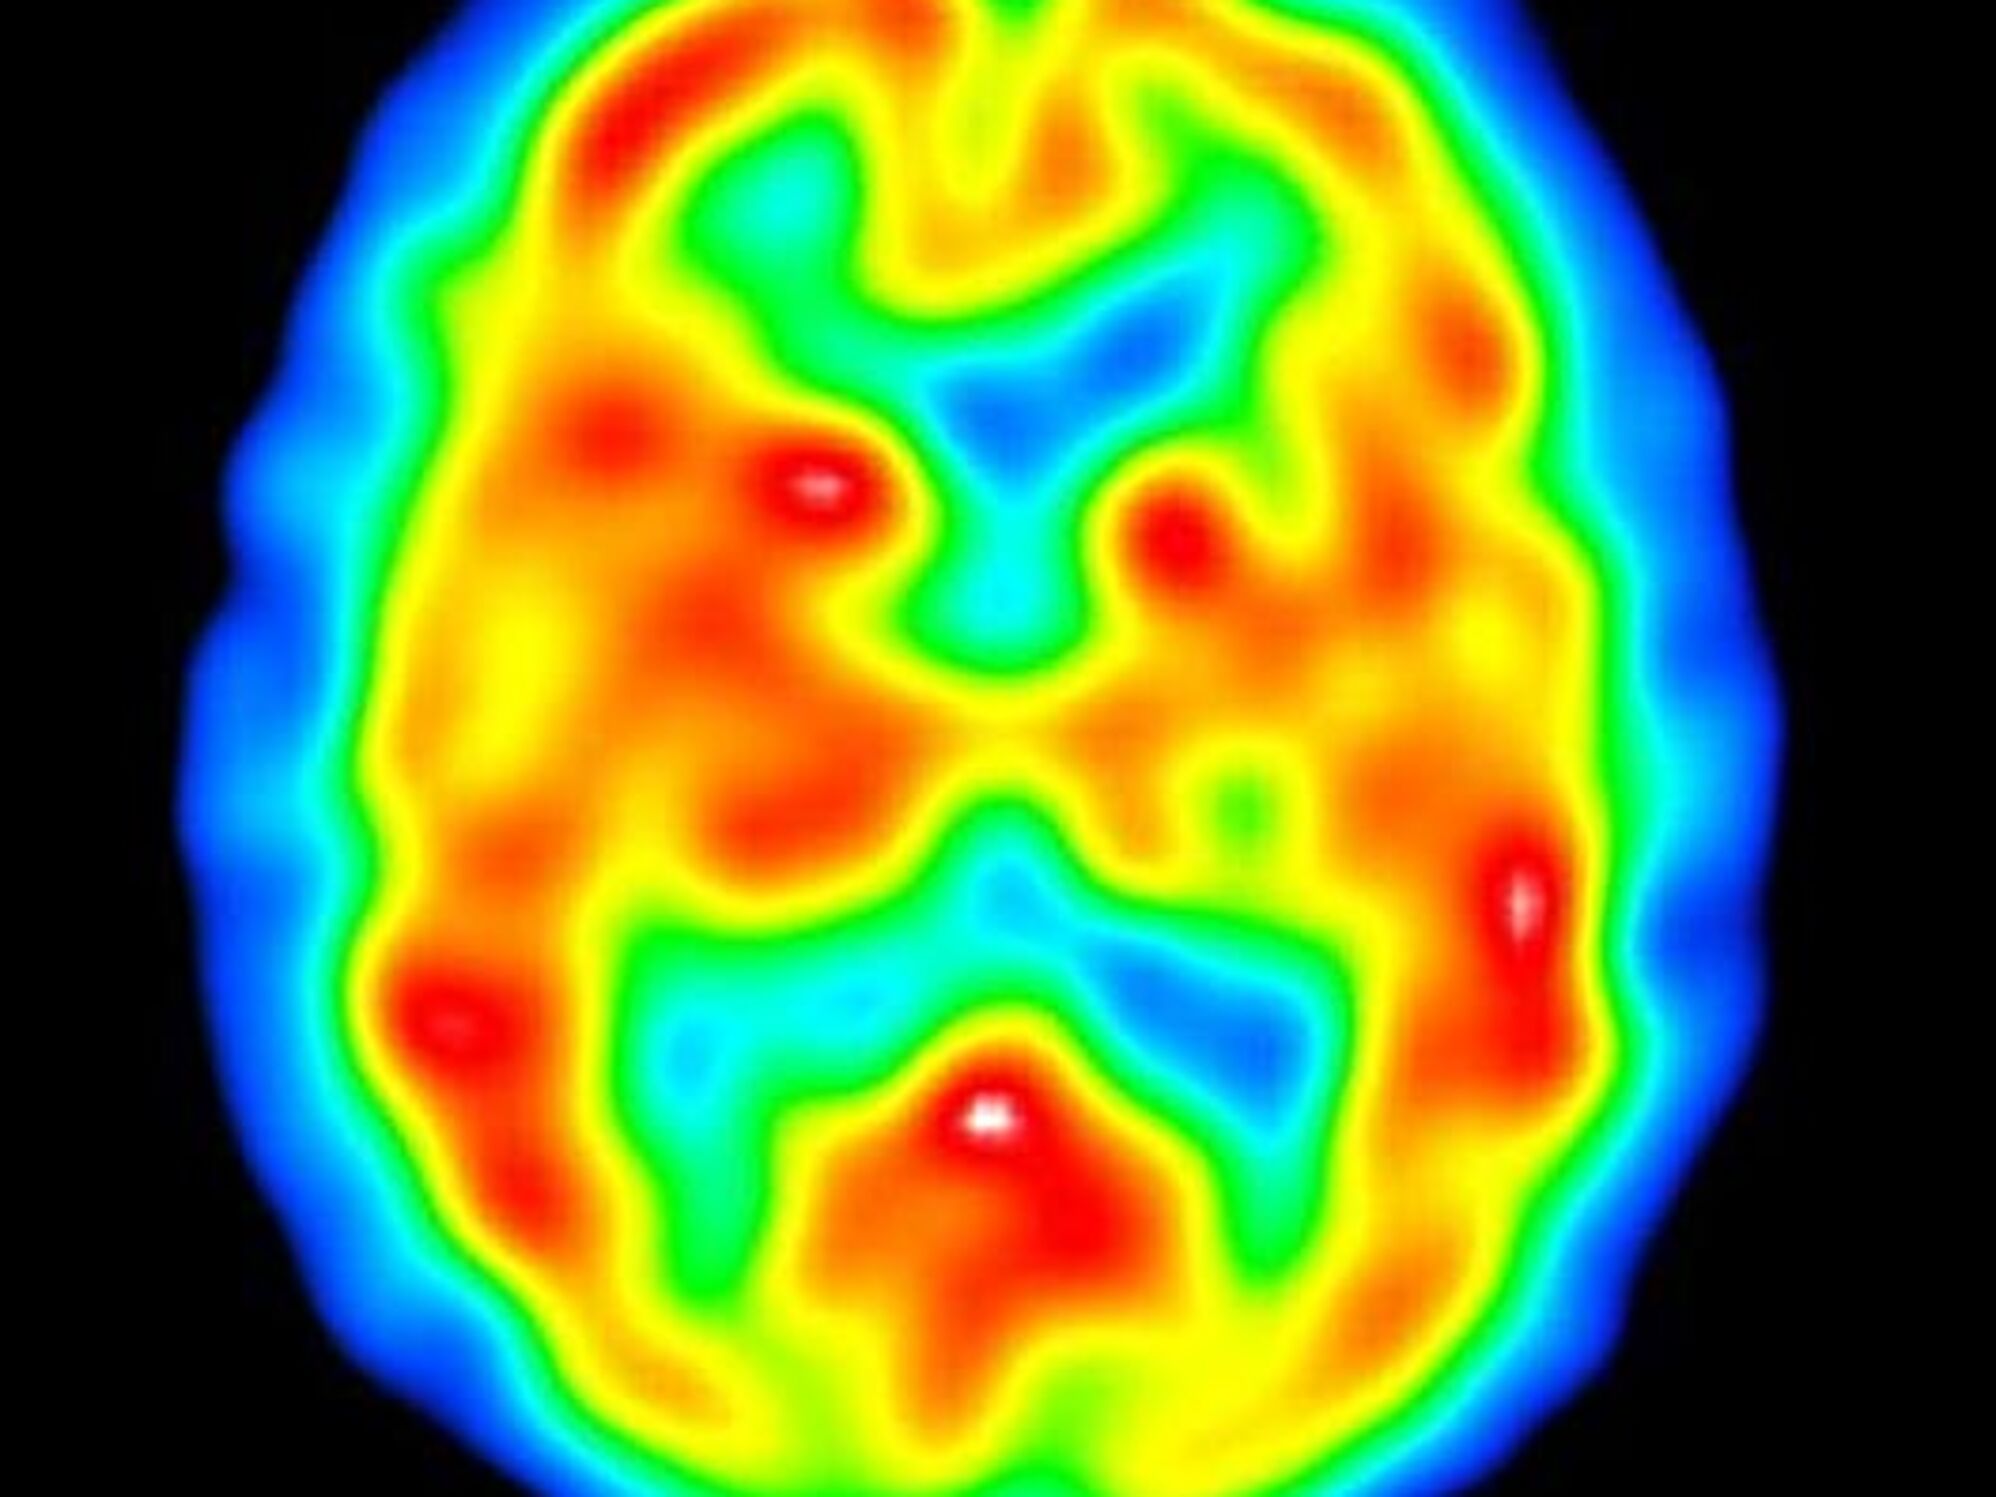

Udvikling af nye former for medicin har givet et gennembrud i behandlingen af nogle af de mest alvorlige psykiske sygdomme.